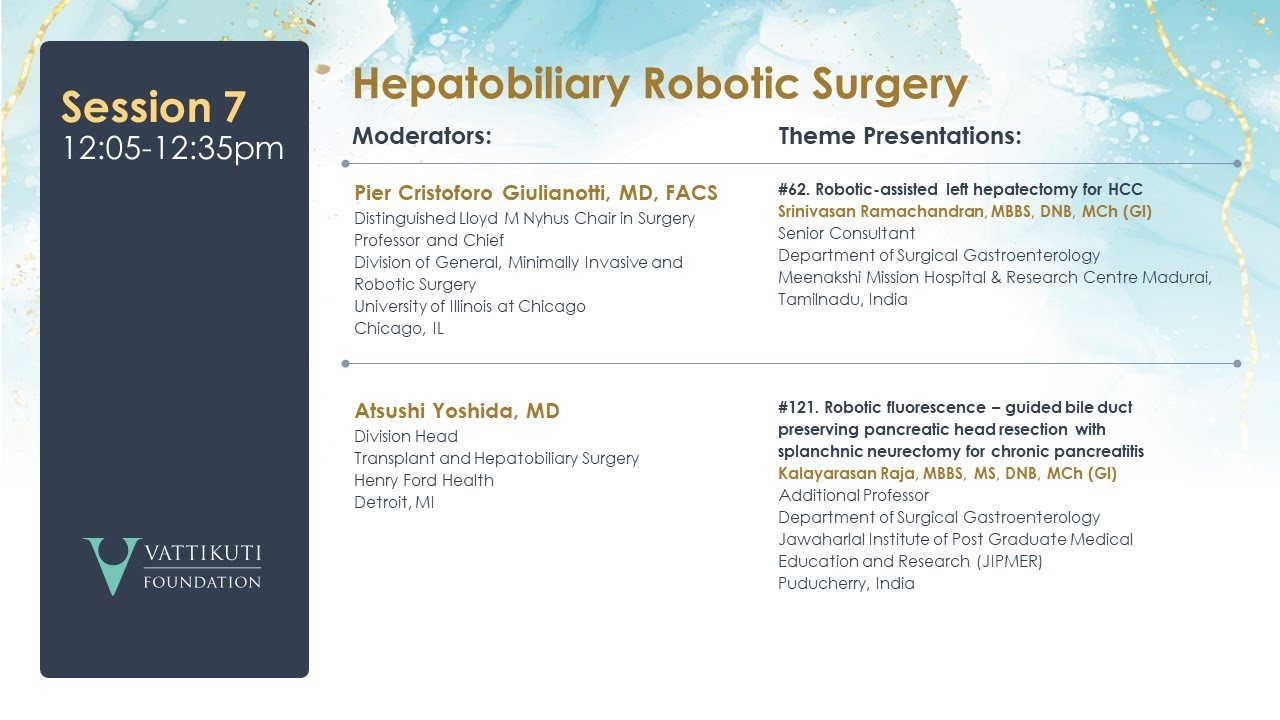

Robot assisted Left Hepatectomy for HCC